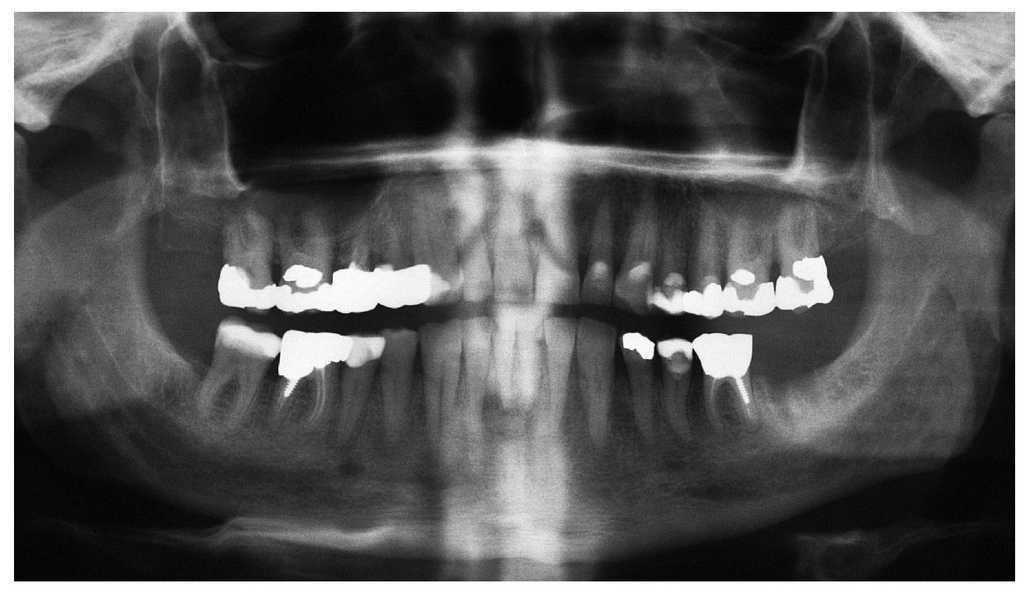

Figura 2a. Radiografía panorámica de un paciente de 69 años sometido a tratamiento con bifosfonatos intravenosos (Zometa) y a tratamiento concomitante con corticosteroides (ambos desde 2004) por un carcinoma de próstata metastatizado. En diciembre de 2006 le fue exodonciado el diente 37 por el odontólogo de cabecera. El paciente fue remitido a nuestra clínica en junio de 2007 por una falta de cicatrización del alvéolo varios meses después de la intervención.

Figura 1a. Radiografía panorámica de un paciente de 58 años con mieloma múltiple conocido (diagnóstico 2005). El paciente fue tratado con bifosfonatos intravenosos (Zometa) en los años 2005 y 2006. El odontólogo del paciente efectuó una extracción del diente 12 en diciembre de 2006 y procedió a su revisión quirúrgica debido a un problema de cicatrización. El paciente acudió al servicio de urgencias de nuestra clínica en julio de 2007 como consecuencia del empeoramiento progresivo de las molestias.

Figura 3a. Radiografía panorámica de una paciente de 68 años con un carcinoma de mama con metástasis óseas. Desde el año 2002 la paciente es tratada periódicamente con bifosfonatos intravenosos (Aredia). En 2006, el odontólogo de la paciente extrajo parte de los dientes de la mandíbula y la totalidad de los dientes superiores. La curación evolucionó de forma tórpida, sobre todo en la mandíbula, y provocó precozmente una dehiscencia de tejidos blandos. Así y todo, esta paciente no nos fue remitida hasta al cabo de 1 año.

Figura 4a. Radiografía panorámica de un paciente de 64 años con carcinoma de próstata metastatizado. El paciente recibe tratamiento con bifosfonatos intravenosos (Zometa) desde 2005. El paciente es portador de una prótesis total desde hace varios años. En junio de 2007 experimentó una sensación de presión debajo de la prótesis en la región mandibular izquierda, que no desapareció después de varios intentos de ajuste por el protésico dental. En julio de 2007, el odontólogo de cabecera remitió al paciente al servicio de urgencias de nuestra clínica.